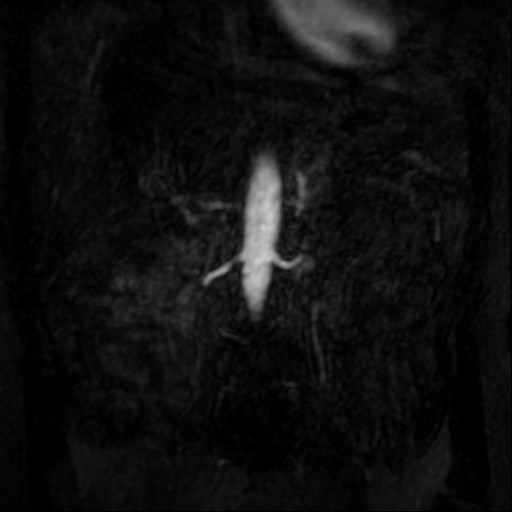

Angio abdominaal